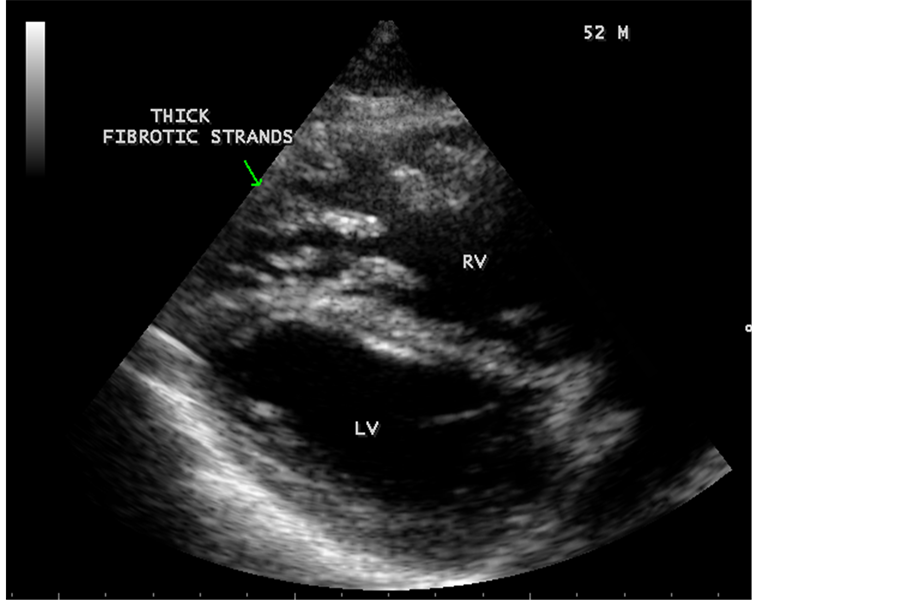

Transthoracic echocardiography revealed strong fibrous strands appearing as “finger like projections” or “cobra-head” appearance in the right ventricular apex due to fibrosis of muscular trabeculae, suggesting right ventricular endomyocardial fibrosis as shown in Figure 3 to Figure 7.

Figure 7. Thick fibrotic stands in RV apex due to fibrosis of muscular trabeculae in Psoriasis.